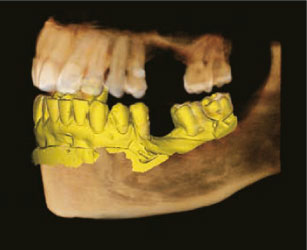

Сегментация зубов и костей

Автоматическое отделение зубов от костей и тела нижней челюсти от верхней челюсти выполняется модулем Segment. При необходимости данные о поверхности можно экспортировать* из программы Ez3D-i в виде отдельных файлов STL.

* При экспорте исследования в программу просмотра данные КТ записываются на диск вместе с моделями зубов и челюстей.

Сегментация зубов

Сегментация кости

Виртуальное удаление зубов

Функция виртуального удаления зубов позволяет проводить планирование функционального ортодонтического лечения без необходимости удаления зубов.

Приятным бонусом к ортодонтическим возможностям сегментации является виртуальное удаление зубов при планировании операции имплантации.

Функция виртуального удаления зубов

Планируемое место имплантации

Подбор имплантата и визуализация размещения